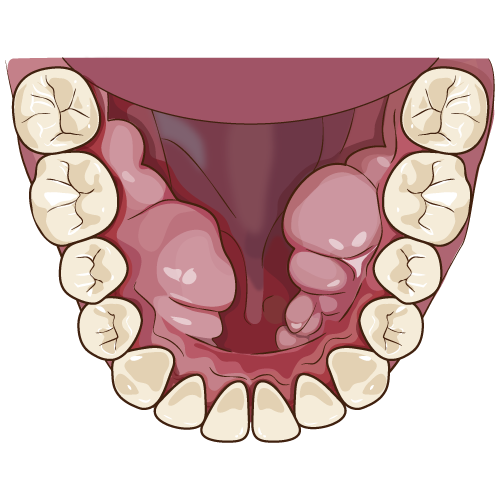

親知らずは、何本ある?

親知らずは、上下左右の4本あります。最近は、初めから生えてこない方も増えてきています。人の体は、必要のない組織は、なくなって行く傾向があり、親知らずも徐々に減少してきています。しかし、まだ多くの方は、親知らずがあり痛みの原因になってしまうことがあります。